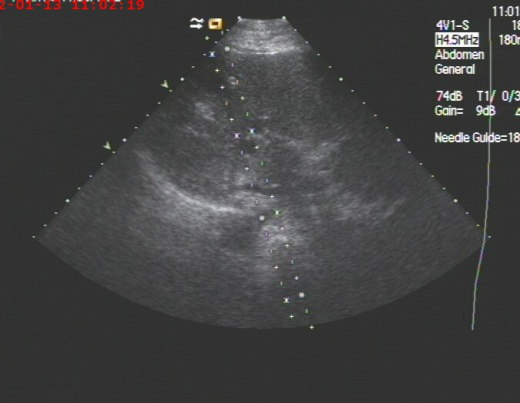

2019年10月呼吸科收治一男性、83岁高龄肺炎合并巨大肝脓肿患者,病人高烧不退,各项感染指标超高,病人既往是多囊肝病人,于10月17日进行超声引导下巨大肝脓肿抽吸治疗术。超声检查局部肝脓肿测量内经达:14cm,术中抽吸灰白色脓液800ml,并送培养,经一个多小时抽吸注药,直至抽出液体清亮,脓肿完全缩小,当即病人病情缓解,高烧消退。送检后显示感染细菌为克雷白氏杆菌,一周后原脓肿再次穿刺治疗,抽出囊液400ml,再次冲洗治疗,经培养已无细菌,随后痊愈出院。